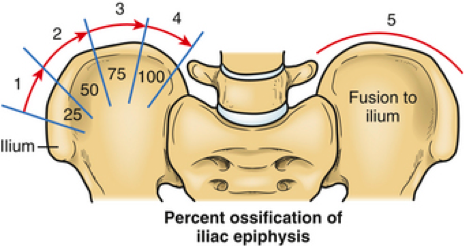

ثالثًا: درجة ريسر (Risser Sign) ونمو الطفل

تُستخدم درجة ريسر لتحديد كمية النمو المتبقية عند الطفل، وهذا مهم جدًا لأن اعوجاج العمود الفقري غالبًا ما يتطور أثناء النمو.

📌 تتدرج درجة ريسر من 0 إلى 5:

- 0: نمو كبير متبقي (خطر أعلى لتطور الحالة)

- 5: اكتمال النمو (خطر أقل للتدهور)

👉 وبالتالي، كلما كان العمر العظمي أصغر، زادت احتمالية زيادة الانحناء. ولهذا السبب، يعتمد الأطباء على هذا المقياس لتحديد سرعة المتابعة وخطة العلاج.